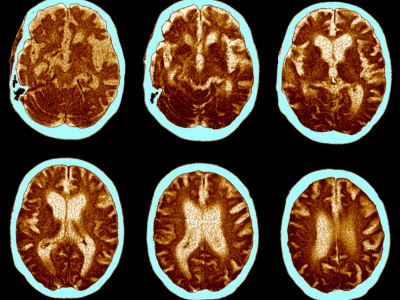

No estágio inicial do Alzheimer, quando os sintomas ainda são sutis, a tomografia computadorizada (TC) e a ressonância magnética (RM) desempenham um papel crucial na detecção precoce da doença. Nestes estágios, as imagens revelam pequenas alterações no cérebro, como a formação de placas de proteína beta-amiloide e emaranhados de proteína tau, que são os primeiros sinais do Alzheimer.

Conforme a doença progride para o estágio intermediário, as imagens de TC e RM se tornam ainda mais reveladoras. Aqui, podemos observar a atrofia cerebral progressiva, o encolhimento de certas áreas do cérebro e a perda de conexões entre as células nervosas. São nesses estágios que os pacientes começam a experimentar sintomas mais evidentes, como lapsos de memória, desorientação e dificuldade de comunicação.

Nos estágios avançados do Alzheimer, as imagens de TC e RM nos levam a uma jornada pelos labirintos da mente, onde a doença exerce seu domínio mais profundo. Aqui, testemunhamos a deterioração generalizada do tecido cerebral, com áreas significativas do cérebro afetadas pela perda de células nervosas e danos estruturais irreversíveis.

Ao longo desta jornada, fica claro que o diagnóstico precoce do Alzheimer é essencial para orientar o tratamento e oferecer a melhor qualidade de vida possível aos pacientes. As imagens de TC e RM não apenas revelam os estágios da doença, mas também fornecem insights valiosos para os médicos e pesquisadores, ajudando-os a desenvolver novas abordagens terapêuticas e aprimorar os cuidados para os pacientes.